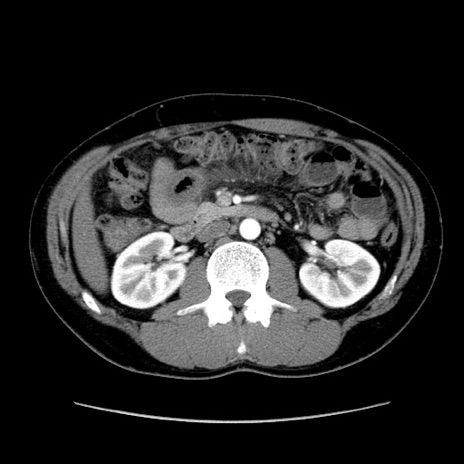

症例36(横断像)

【症例】20歳代 男性

【主訴】心窩部痛

【現病歴】今朝より上腹部痛あり。一旦軽快していたが再度出現したため救急要請。昨日夕に白身の魚を含む刺身を食べた。

【身体所見】BP 136/89mmHg、HR 74/min、BT 37.0℃、腹部:膨満、軟、心窩部に圧痛あり。反跳痛なし、筋性防御なし、腸雑音やや亢進あり。

【データ】WBC 17700、CRP 0.48